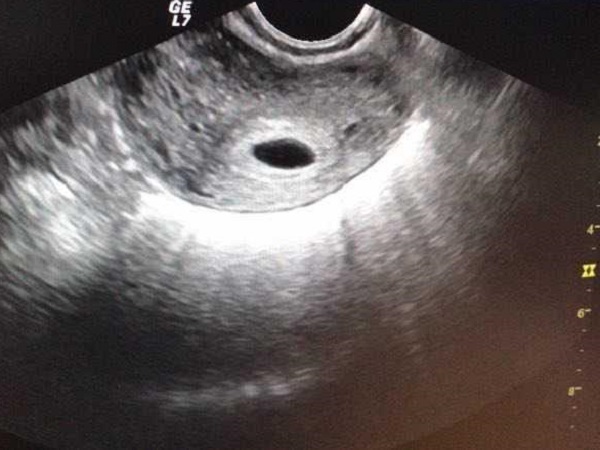

近年来,随着辅助生殖技术的快速发展,试管婴儿已成为许多不孕不育家庭的选择。然而,在试管助孕过程中,有些患者可能会遇到“空卵泡”的情况。所谓空卵,是指在促排卵周期或自然周期中,血清雌二醇( E2)水平及B超下监测卵泡发育良好, 但穿刺取卵时未获得卵母细胞。就像是花生一样,有的花生看起来大而成熟,但是剥开后却是空的,或者花生粒很小。那么这究竟是为什么呢?